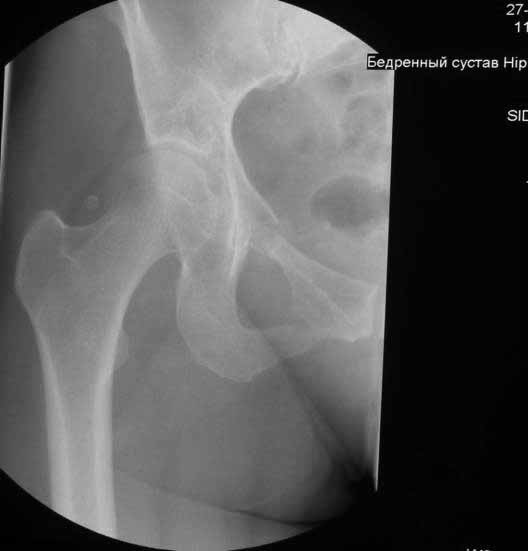

Уважаемые коллеги. Хотелось бы услышать мнения и советы по представляемому случаю. Пациентка 45 лет. Бесцементное эндопротезирование левого тазобедренного сустава 6 лет назад (впадина RM, Mathys, металл-металл, ножка Зульцеровская). За 10 лет до протезирования – коррегирующая остеотомия бедренной кости, которая не срослась в течение года до удаления пластины, а затем срослась в течение 3 месяцев иммобилизации в кокситной повязке. После протезирования получилось наблюдать пациентку почти постоянно, поскольку через 2 года синтезировал ей лодыжки на оперированной стороне, затем, через несколько месяцев удалил фиксаторы, а в 2009г. резецировал мениск на противоположной стороне. Боли все эти годы не беспокоили. Пациентка чуть выше среднего роста, вес тела нормальный. Физические нагрузки переносила хорошо. Работает на 7 этаже без лифта. Год назад экстирпация матки по поводу лейомиомы больших размеров. Несколько месяцев назад появились боли в области левого тазобедренного сустава. При рентгеновском и КТ исследованиях (июль с.г.) – нестабильность тазового компонента. От предложенной замены протеза пациентка на тот момент, слава богу, отказалась. Через какое то время боли в области левого тазобедренного сустава практически полностью прошли, а около 2 месяцев назад появилось ощущение патологической подвижности таза и боли в паху справа, которые через некоторое время уменьшились, а потом снова усилились после значительных физических нагрузок (много ходила по песку на пляже, носила тяжести). Ежедневно принимала диклофенак. На рентгенограммах – переломы правой лонной кости. Сейчас госпитализирована из-за болей в паху справа. Боли слева не беспокоят. На фоне снижения нагрузок в стационаре боли значимо уменьшились. Способна ходить без средств дополнительной опоры.В анализах крови чуть повышены трансаминазы и гамма-ГТ, моча без особенностей.

Вопросы: -правильно ли я расцениваю переломы как стрессовые на фоне неполноценного таза (pelvic insufficiency stress fractures)? -Можно ли так же расценить ситуацию на стороне протеза и, соответственно, не торопиться с ревизией, рассчитывая на вторичную стабилизацию? Уж больно не хочется менять ножку. -Если думать о ревизии, то когда? На представленных снимках тазобедренный сустав до и сразу после операции, затем 2 снимка 2009г., когда ничего не беспокоило, затем КТ 2-х месячной давности и вчерашние рентгенограммы обоих тазобедренных суставов.